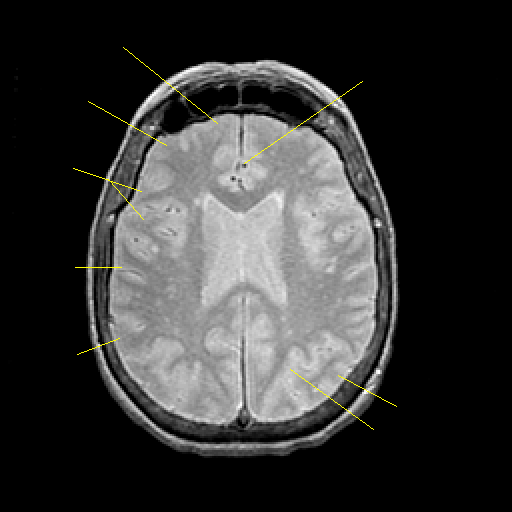

Proton density-weighted structural MR: Slice 33

Slice 33

Pointers

Labeled